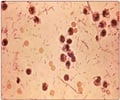

Diagnosis of Hepatitis A

- A blood test is needed to detect circulating antibodies to the hepatitis A virus.